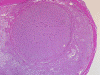

On low-magnification, cross section of the optic nerve gives a "double barrel" structure. The general outline of an optic nerve can still be appreciated (delimted by Þ in Panel A). There is a moderately cellular population of cells in between the dural sheath ( in Panel A) and the optic nerve. On medium-magnification, the vascular septa of the optic nerve is preserved (Panel B). On high-magnification, the optic nerve contains a mixture of cells with enlarged, mildly pleomorphic nuclei that are neoplastic astrocytes. Some cells with small nuclei are present and probably represent residual and reactive non-neoplastic astrocytes (Panel C and D). Cytoplasmic processes of some of tumor cells appear finely fibrillary (Panel C) while others are corase (Panel D). The cells in between the optic nerve and the dura is a mixture of irregular, hypercellular islands of neoplastic glial cells (delimted by Þ in Panel E) and hypocellular islands of slightly eosinophic, spindle cells. The later population represents reactive proliferation of meningothelial cells. The cytologic features are better appreciated in high-magnification (Panel F).

Grossly ONG grows within the dural sheath to produce a fusiform enlargement.  The neoplasm occasionally invades beyond the optic dural sheath.

Microscopically, ONG in children are almost all pilocytic astrocytomas. The optic nerve is expanded. The fibrovascular septa within the optic nerve are separated by the tumor cells but the structure can still be well recognized as an optic nerve on cross section. Three major patterns are recognized 1. In the first pattern, the tumor is finely reticulated. In the second pattern, the tumor has microscysts and is coarsely reticulated. In the third pattern, the tumor cells are coarsely fibrillated, spindle shaped, and form bundles. There is minimal pleomorphism in the nuclei and it is not always easy to separate the neoplastic cells from adjacent reactive gliosis. There is a usually lack in mitotic activity, endothelial proliferation, and necrosis. Immunohistochemistry, the tumor cells are strongly reactive for glial fibrillary acidic protein (GFAP).